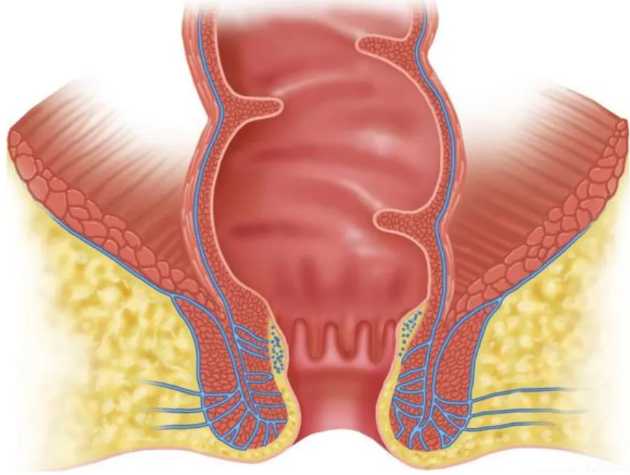

因此直肠肛门的形态是上大下小,上松下紧的结构。当强行有异物进入后,括约肌会收缩恢复到紧闭状态,阻止异物轻易排出。

过程中,异物很容易就到达了直肠。直肠名叫直肠,其实是弯曲的,大大增加了取出异物的难度。